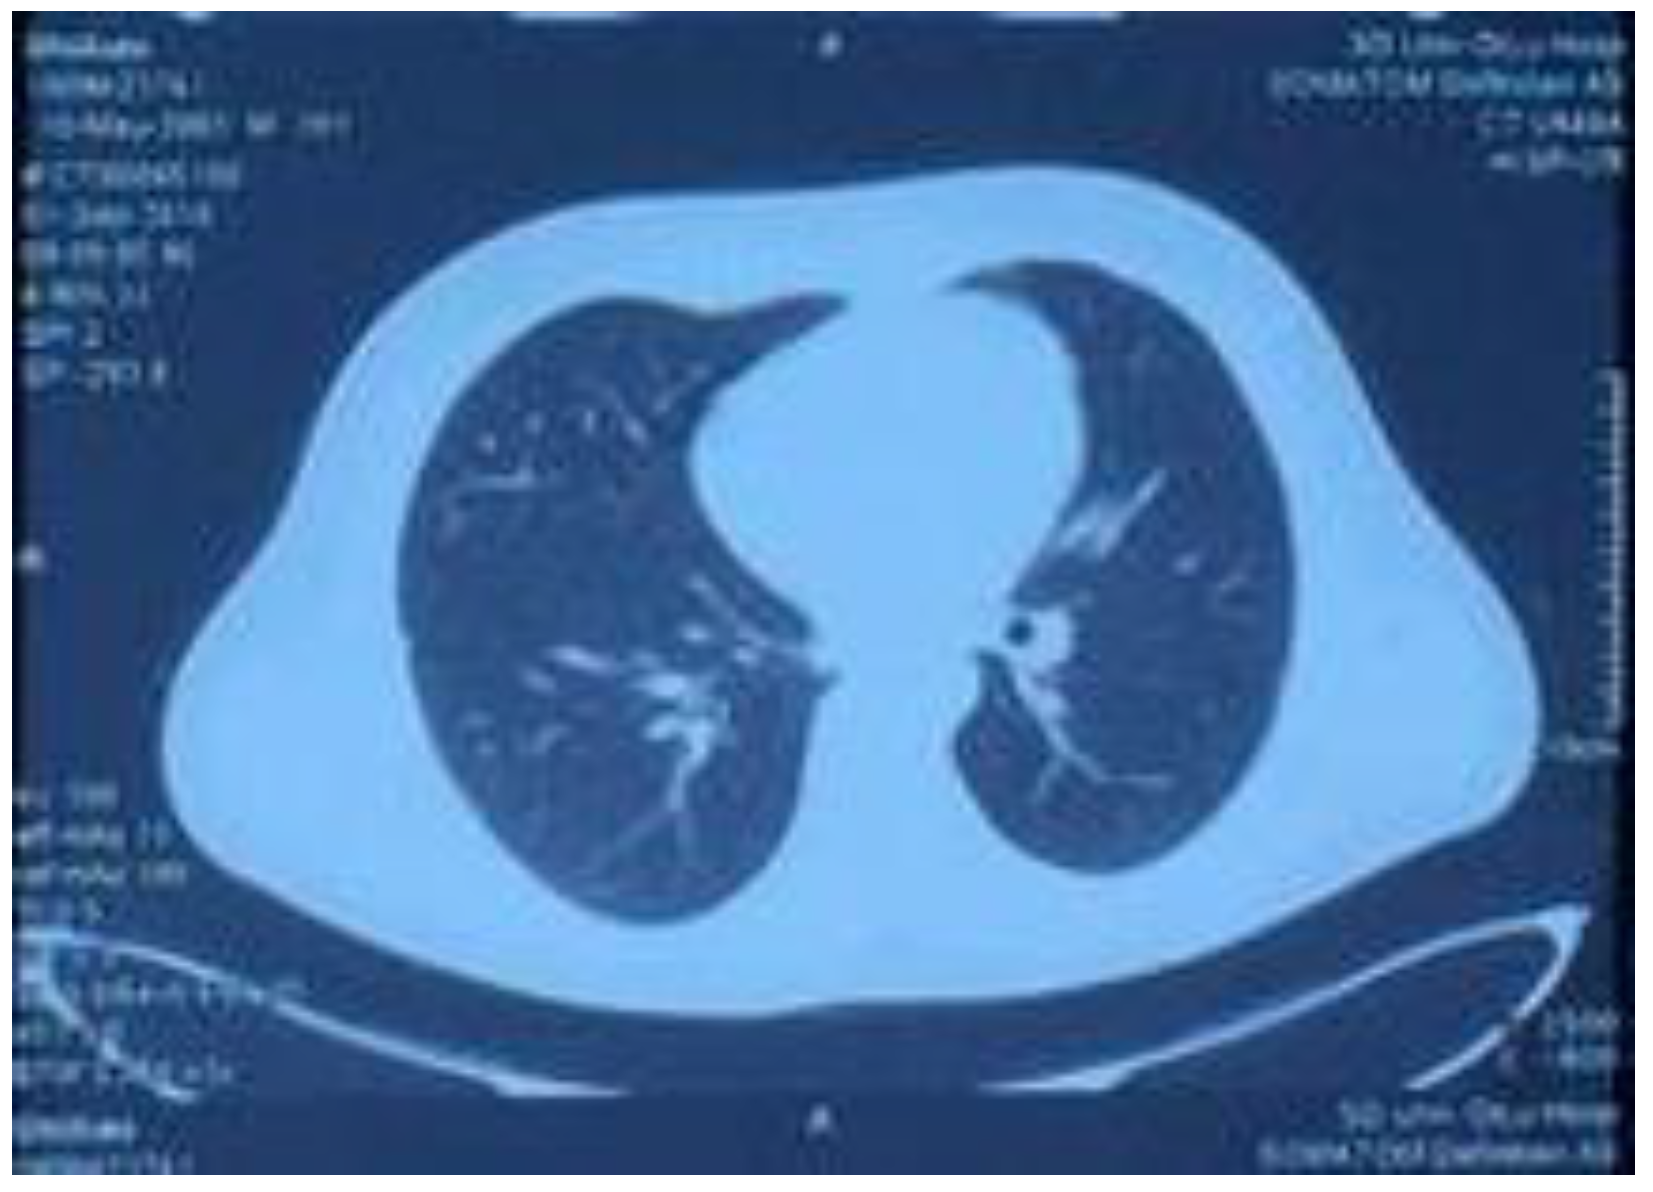

Figure 3.

Lung CT performed on 15 August 2018, showing increased texture in both lungs, a patchy high-density shadow, unobstructed bronchi above the segment, and a patchy high-density shadow in the posterior segment of the lower lobe of the right lung.

On 15 August, the patient started coughing up yellow phlegm and had another fever spike; the highest reading reaching 38.9 °C. Sputum cultures and chest computed tomography examination were performed (Figure 4). The culture test results showed Pseudomonas aeruginosa and Escherichia coli growth. Consequently, the drug regimen was adjusted to imipenem 500 mg IV infusion Q 6 h according to the drug sensitivity test. The CT results showed increased texture of both lungs, a patchy high-density shadow, unobstructed bronchi above the segment, and a patchy high-density shadow of the lower and posterior segment of the right lung. Other laboratory tests revealed white blood cells, 7.12 × 109/L; neutrophils ratio, 67.10%; red blood cells, 3.92 × 1012/L; platelets, 248 × 109/L; serum myoglobin, 111.60 ng/mL; creatine kinase isoenzyme, 7.30 ng/mL; serum hypersensitive troponin I, 356.79 ng/L; and NT-probNP, 594.70 pg/mL. (Table 1) The patient’s symptoms significantly improved after weaning and adjusting antibiotics, and his body temperature gradually normalized. On 20 August, drug administration was stopped, and the patient’s condition improved; therefore, he was discharged. After discharge, he continued to take Jinshuibao and Qishen Yiqi pills orally.